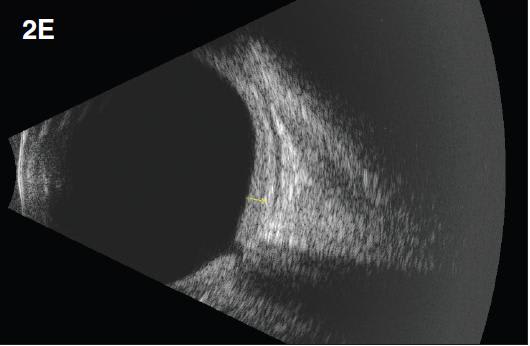

Figure 2. Diffuse choroidal hemangioma. The patient was a nine-year-old boy with history of Sturge-Weber syndrome, referred due to decreased vision (20/200) and subretinal fluid in the right eye. The fundus exam revealed retinal pigment epithelium mottling around the optic nerve with a surrounding cuff of subretinal fluid (A). B-scan ultrasonography demonstrated a solid, highly echogenic lesion, with diffuse choroidal thickening (B). OCT showed subretinal fluid with cystic spaces in the outer retinal layers (C). One year after treatment with external beam radiotherapy (20 Gy in 10 fractions, 2 Gy/fraction), the fundus exam revealed a regressed hemangioma (D). Tumor regression was confirmed by B-scan ultrasonography (E). Concomitant resolution of subretinal fluid was noted on OCT (F). Visual acuity improved to 20/60.

B-scan ultrasonography demonstrates solid, highly echogenic lesions, with diffuse choroidal thickening (Figure 2b), and high internal reflectivity on A-scan. Early hyperfluorescence with persistence of hyperfluorescence through the late phases of the angiogram are seen with fluorescein angiography. Similar findings are observed on ICG, with a characteristic lacy intrinsic vascular pattern, with a diffuse distribution.16 OCT may be used to confirm the presence of subretinal fluid (Figure 2c).